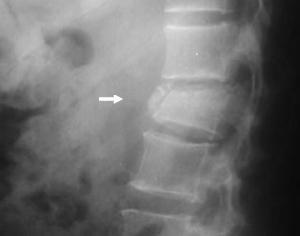

• Radiología columna dorso - lumbar

Rx. Columna dorso lumbar frente y lateral. muestra disminución del espacio vertebral L1, caracterizado por disminución de su altura, con fragmentación del cuerpo vertebral y escaso desplazamiento posterior.

Corte sagital

Flecha: Observe la fractura del cuerpo vertebral L1, con escaso compromiso del canal medular.